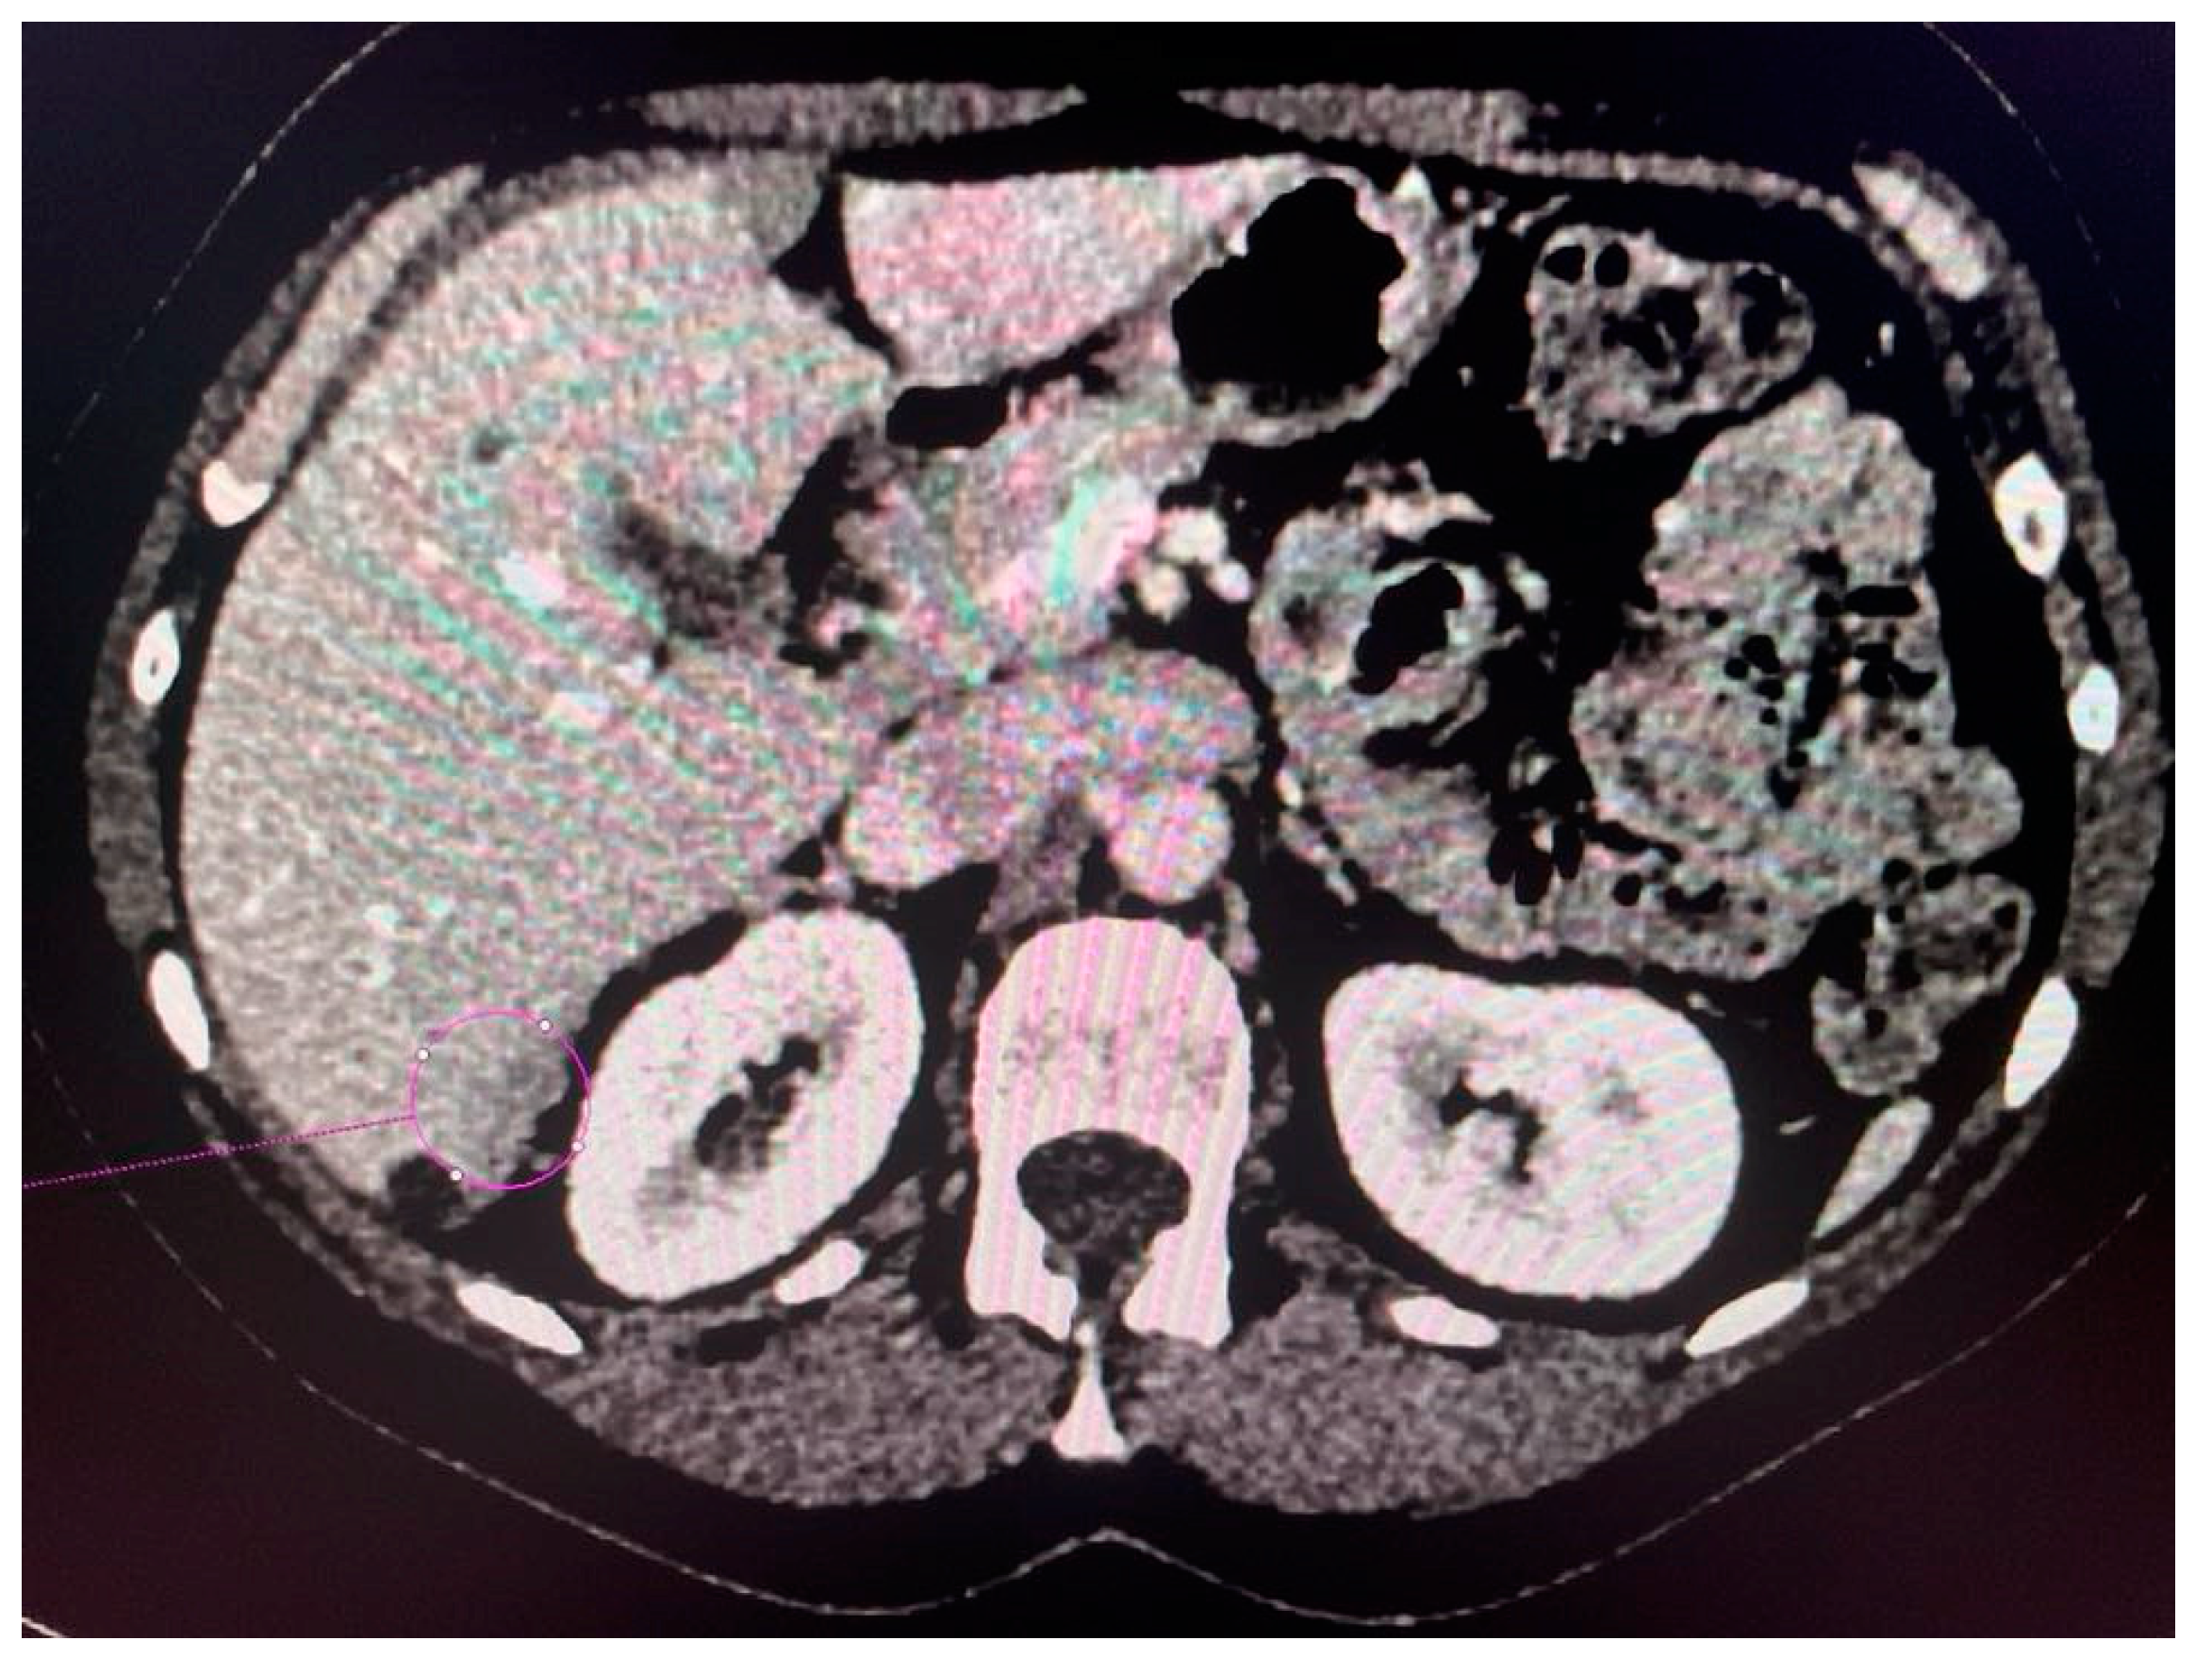

2.3. Computed Tomography Examination